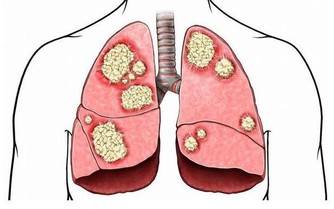

●如果你担心你的胆固醇 美国加利福尼亚州沙托斯健康研究中心主任、营养学专家史皮尔研究表明,假如每天摄食相当于400卡热量的葡萄干,能有效降低血中胆固醇的8%,同时还能抑制血中坏胆固醇的氧化。 ●如果你有入厕烦恼 葡萄干能改善直肠的健康,因为葡萄干含有纤维和酒石酸,能让排泄物快速通过直肠,减少污物在肠中停留的时间。 ●更令人兴奋的是 葡萄干中含有一种称为白黎卢醇的成分,它能有效地防止细胞恶变并抑制恶性肿瘤的增长 我知道葡萄干是好东西,但我不知道原来它这么好!!!真的太让我意外了...!